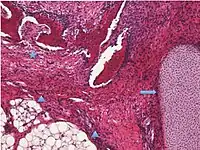

| Sex cord-stromal tumor | Ovarian fibroma | 1.5% | 0% | Spindle-shaped fibroblastic cells and abundant collagen.[8] | ![]() |